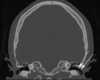

11

Q

A

C3/4 facet joint

12

Q

A

cribiform plate of ethmoid bone

13

Q

A

right head of caudate nucleus

14

Q

A

tegmentum of pons

15

Q

A

cerebral aqueduct

aka acqueduct of sylvius

16

Q

A

interhemispheric fissure

17

Q

A

3rd ventricle

18

Q

A

pituitary fossa

aka sell turcica

19

Q

A

external occipital protruberance